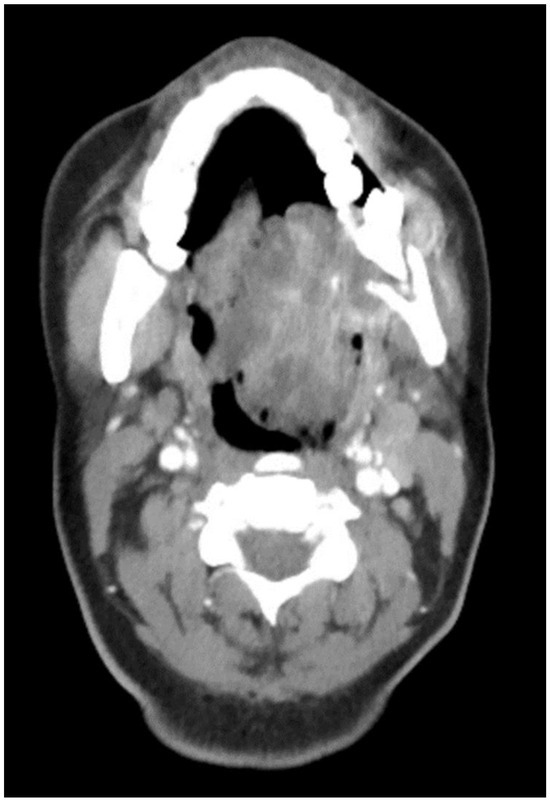

Figure 3.

CT neck with contrast showing the enlarged lymph node at level 1B.